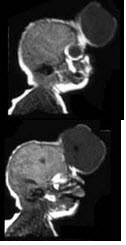

根据图示,肌营养不良的类型为( )

A:面肩肱型肌营养不良

B:Duchenne肌营养不良

C:Becker肌营养不良

D:肢带型肌营养不良

E:眼肌型肌营养不良